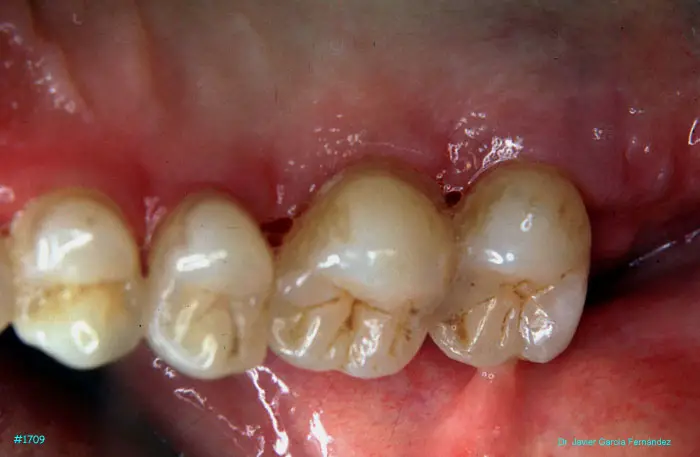

image 220